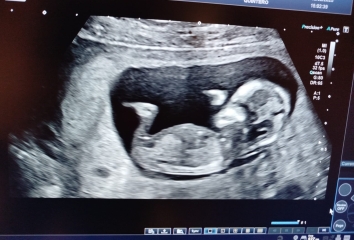

Hi all! Sorry I´ve been away from mumsnet for a while. I´ve been really busy lately and also everytime I thought about reading the thread I couldn´t shake the feeling that I was making everything up. Sometimes I can´t believe it´s happening buuuuut....

I had another scan today and saw the babies and for today it all seems real again 😂I will post the pictures (hope the site allows me to do it).

They all are in different sacs with individual placentas. All seems well.

OMG! It's triplets!!!